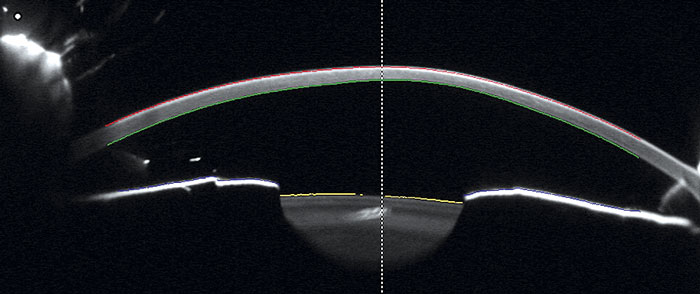

Figur 3. Intermediär uveit. Överst: Vitrit med glaskroppsgrumlingar som förhind­rar insyn till ögonbotten. Nederst t v: Fluoresceinangiografi visar läckage i gula fläcken på grund av makulaödem. Nederst t h: Snitt av näthinnan taget med optisk koherenstomografi som visar svullnad i gula fläcken.